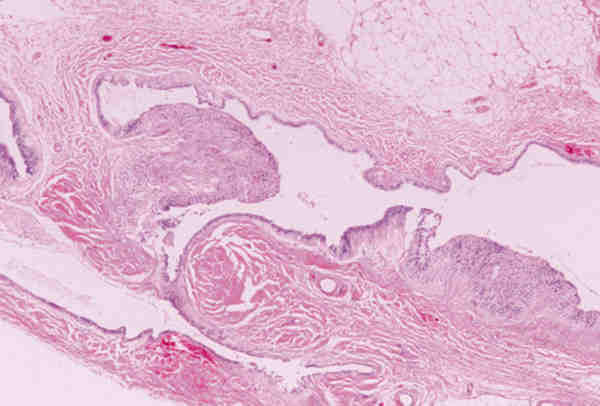

* Quistes epidermoides: Presentan un epitelio poliestratificado

queratinizante sin anejos en su pared (figura 3).

Figura 3. Quiste epidermoide. En la pared no existen anejos y

está revestido por epitelio escamoso queratinizante.

Ambas lesiones suelen aparecer en los primeros meses de vida en forma de

nódulos subcutáneos situados sobre el anillo orbitario, aunque a veces

también existen en zonas más profundas de la órbita. Son lesiones benignas

que no infiltran las estructuras adyacentes y se tratan con extirpación

quirúrgica simple. Lesiones quísticas idénticas pueden desarrollarse

secundariamente por implantación traumáticas o yatrogénica.